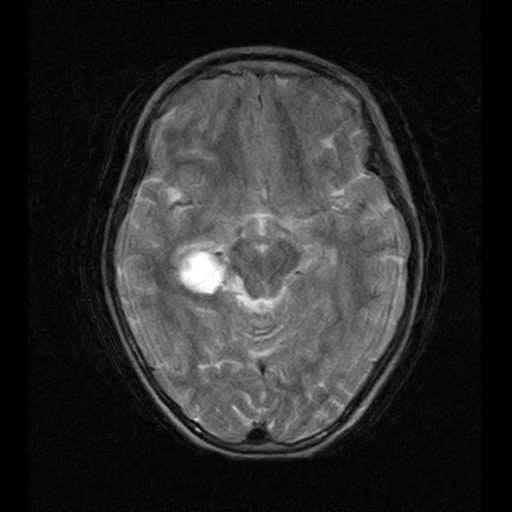

Семирічній франківчанці потрібна допомога на операцію (реквізити)

Семирічній Марічці з Івано-Франківська діагностували пухлину головного мозку.

Дівчинці потрібна операція за кордоном, інформує Фіртка.